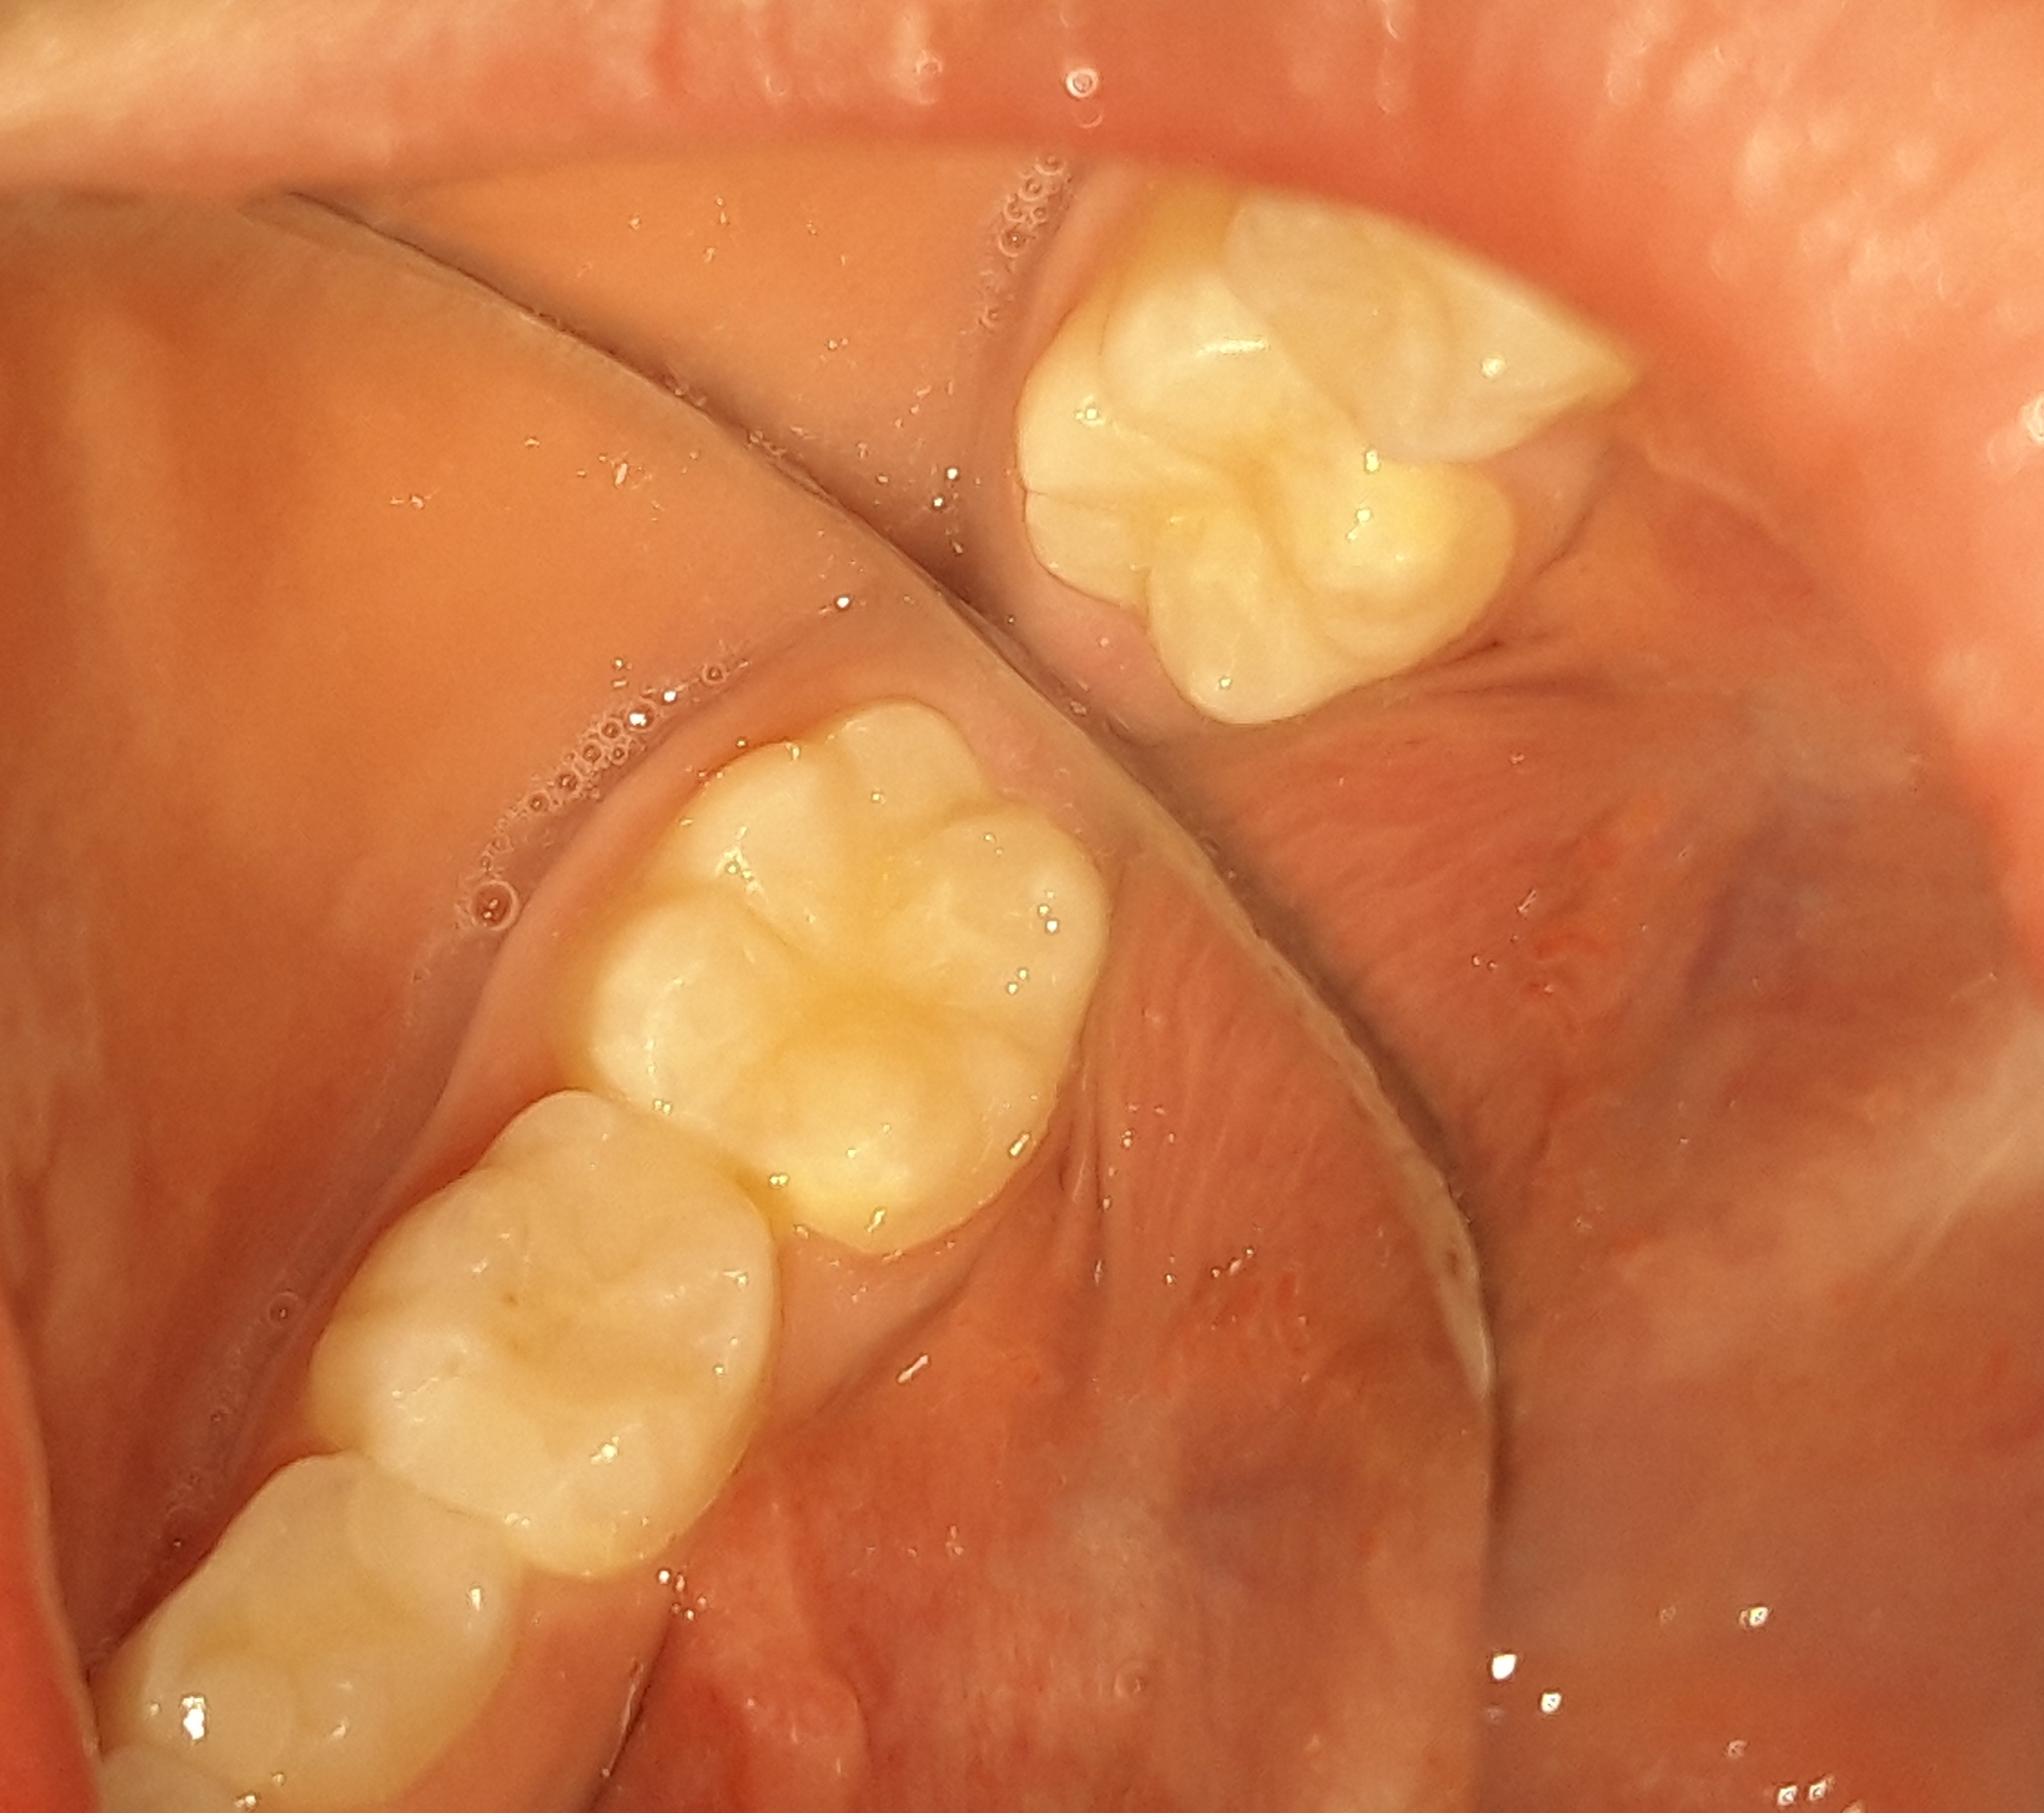

Η μικρή ασθενής προσήλθε για τον τυπικό ετήσιο έλεγχο. Συστήθηκε η προληπτική κάλυψη των δεύτερων μόνιμων γομφίων (sealant), δεδομένου οτι το κορίτσι είχε ήδη 4 σφραγισμένα δόντια και επομένως υπάρχει τερηδονική δραστηριότητα στο στόμα της. Με την προληπτική κάλυψη των δοντιών προστατεύονται οι μασητικές επιφάνειες αυτών από πιθανό τερηδονισμό τους.Τα sealants είναι καλό να γίνονται σε όλους τους μόνιμους γομφίους των δοντιών. Η πρόληψη είναι η καλύτερη θεραπεία.

ΠΡΙΝ

ΜΕΤΑ